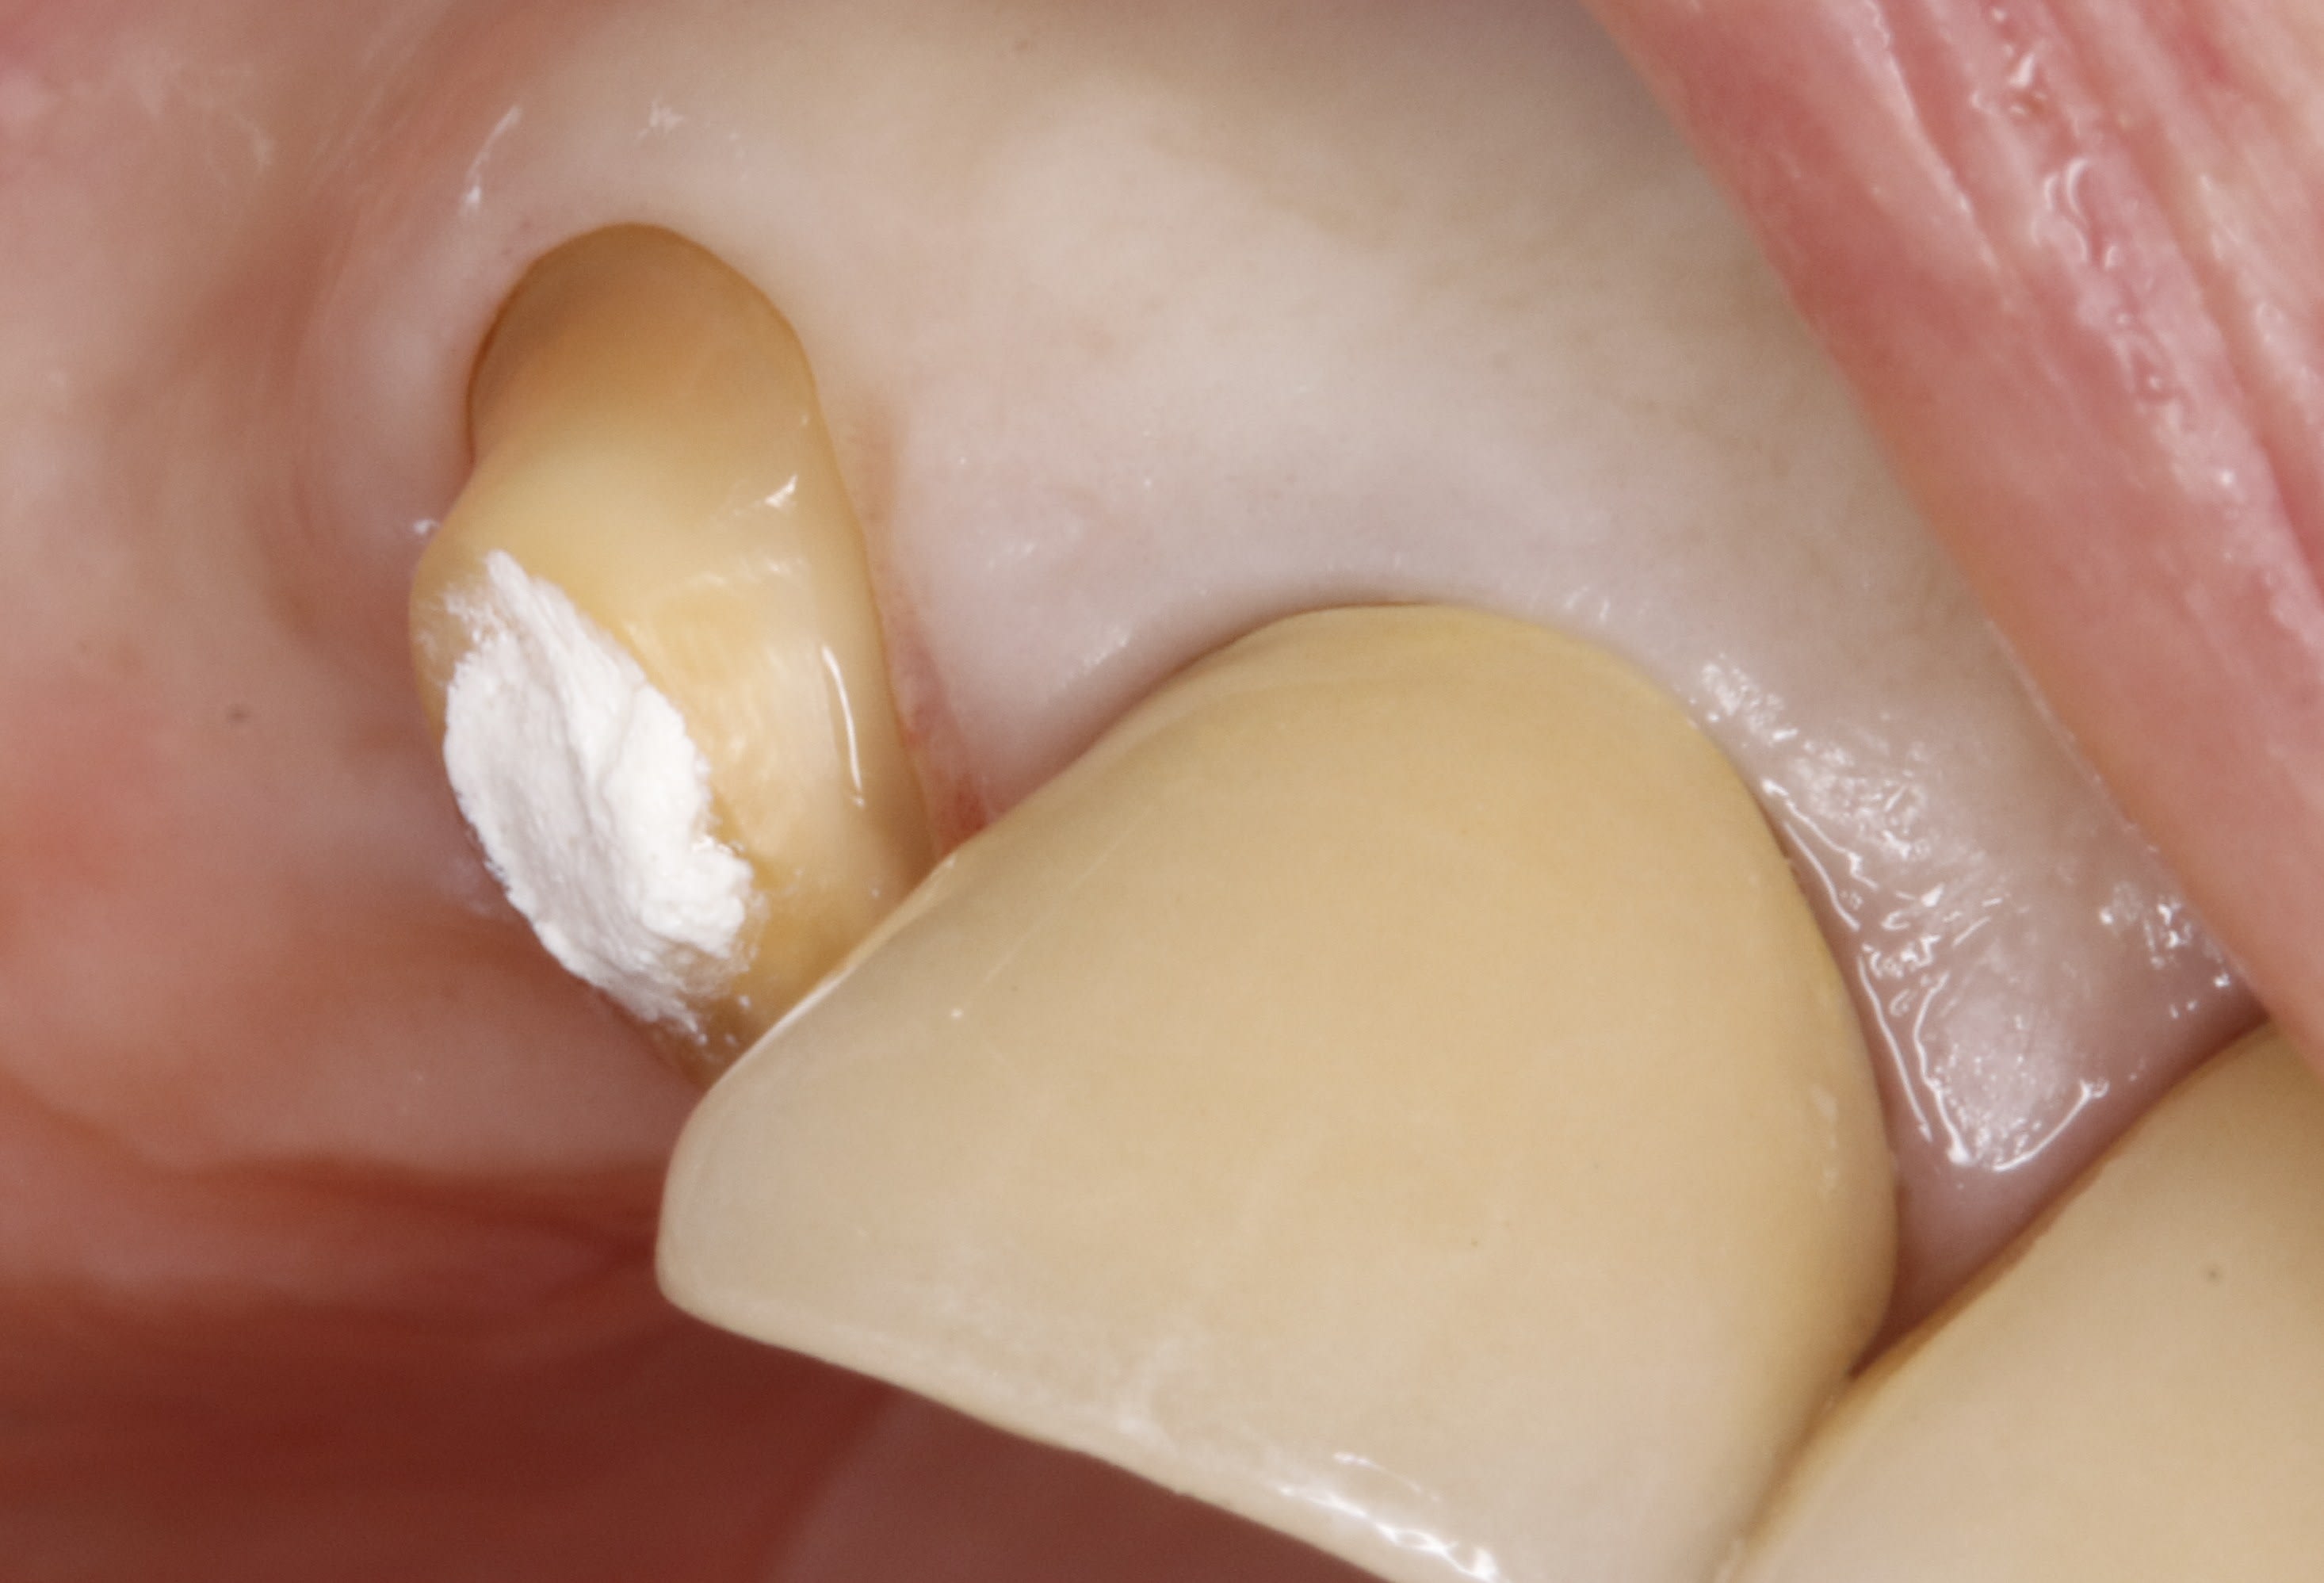

et pour finir , ç est le cas de ma 25 de la page 4 .

on a donc pris l empreinte apres avoir descendu les limites la semaine passée .

aujourd'hui , il est comme ça : la gencive a effectivement recouvert les limites , mais gentiment , tranquille .

et il suffit de sceller la ceram , et hop , on en parle plus .

12 vurnow - Eugenol